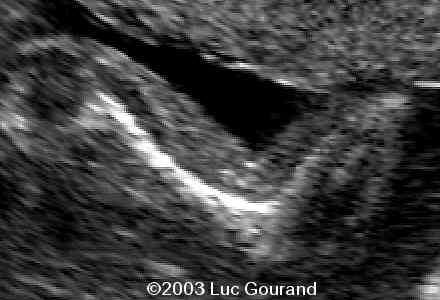

The following images were obtained in from third trimester fetus.

The following images were obtained in from second trimester fetus. The head demonstrated a cloverleaf skull, frontal bossing, proptosis

Radiohumeral ankylosis was seen at the level of the arm, the thumb and toes are broad.

case0093-14

case0093-15